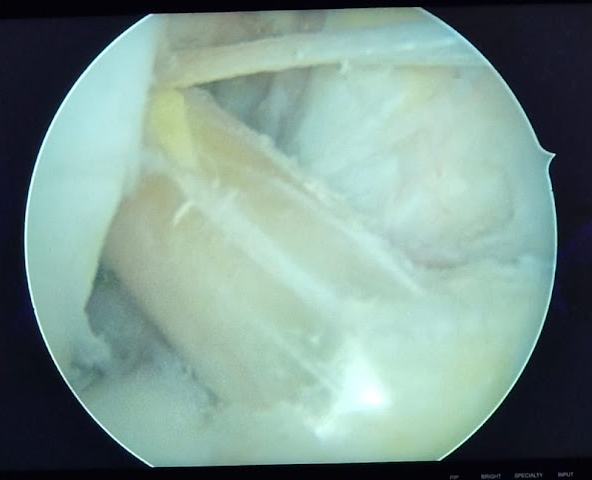

Artroskopi

Artroskopi; menisküs yırtıkları, ön çapraz bağ yaralanmaları gibi diz hastalıklarında ve omuz kas yırtıklarında kullanılan modern kapalı cerrahi yöntemdir. Son 10 yılda binlerce hastanın sağlığına kavuşmasına, günlük yaşantısına, işe ve spora güvenle dönmesine yardımcı olduk.

Menisküs

Menisküs ve Ön Çapraz Bağ Yaralanmaları

Spor yapan gençlerden günlük yaşamda ani hareket eden kişilere kadar birçok insanın başına gelebilecek en yaygın diz yaralanmaları, menisküs yırtıkları, ön çapraz bağ (ACL) yaralanmalarıdır...